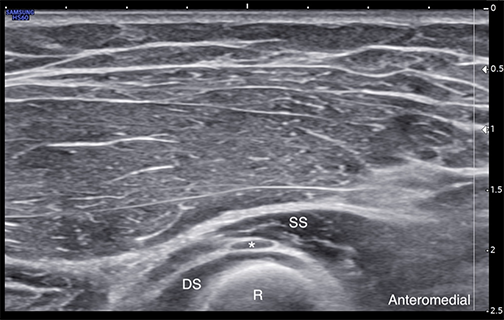

Labeled short-axis ultrasound image of the deep motor branch of the radial nerve a few millimeters distal to the arcade of Frohse. DS = Supinator muscle deep head SS = Supinator muscle superficial head R = Radius